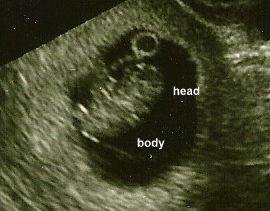

10 weeks

7/29/10